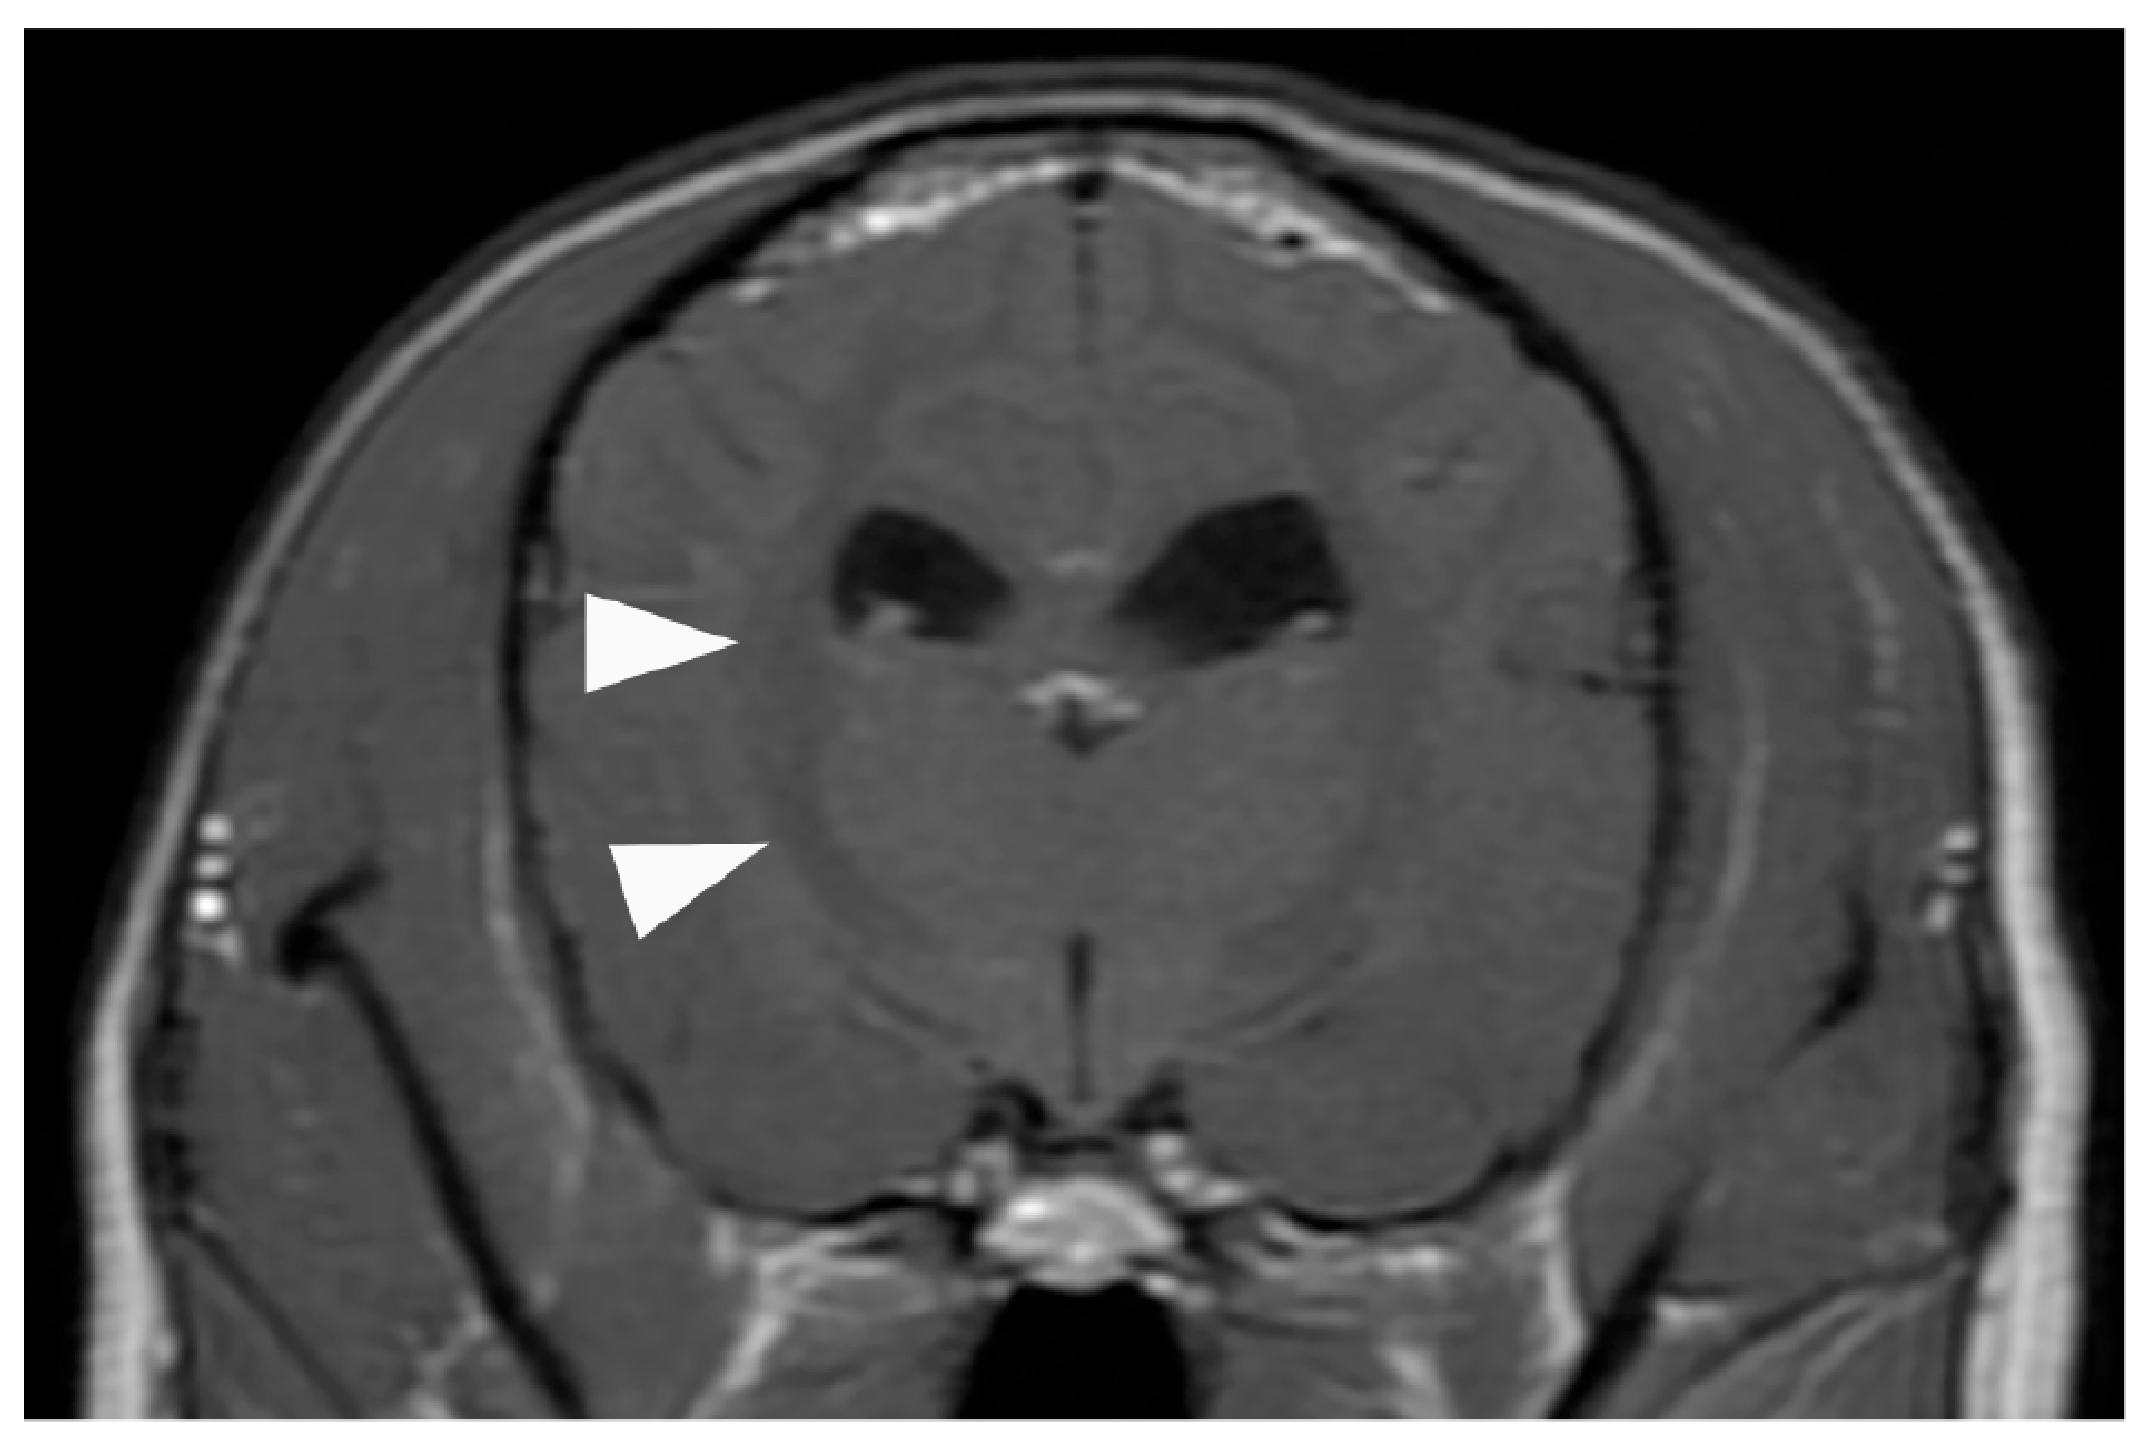

2. Case Presentation